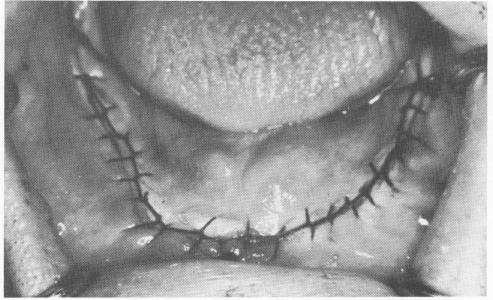

After the necessary impressions have been made, the site is sutured closed. This may be done with interrupted sutures, or surgical ties, which are a series of separate sutures placed about %4 inch apart. The knots should be made to one side of the wound so that they will not press on it. Alternately, the sutures may be continuous, uniting the wound from one end to the other. Suturing in this manner is started by passing the needle through one edge of the wound and tying a simple knot. The edges of the wound are then pierced successively, making sure that the thread directly behind the needle is always under it, until the end of the wound is reached and closed with a terminal surgical knot (Fig. 12-21) . Both interrupted and continuous suturing close the wound by bringing the edges together.

Fig. 12-21. There must always be enough sutures to completely close the wound. This case shows continuous suturing completely around the arch from retromolar pad to retromolar pad.

1 Continuous suturing around arch from retromolar pad to retromolar pad